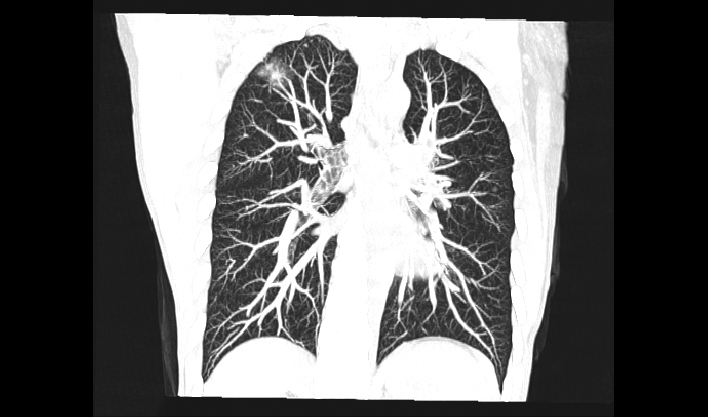

El detector de cuerpo ancho de cuarta generación, de desarrollo propio, cubre más áreas de tejido.

La matriz de reconstrucción de 1024*1024 amplía los datos de la imagen cuatro veces. Combinado con imágenes de corte fina, incluso las lesiones más invisibles son claramente visibles.

Captura instantánea para evitar artefactos por movimiento respiratorio, lo que mejora la tasa de éxito de los exámenes.